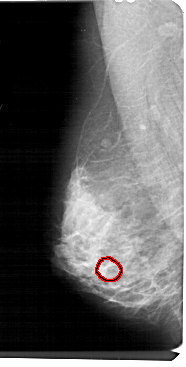

A_1449_1.LEFT_MLO

LEFT_MLO LINES 5491 PIXELS_PER_LINE 2776 BITS_PER_PIXEL 12 RESOLUTION 43.5 OVERLAY

FILE: A_1449_1.LEFT_MLO.OVERLAY

TOTAL_ABNORMALITIES 1

ABNORMALITY 1

LESION_TYPE CALCIFICATION TYPE AMORPHOUS DISTRIBUTION CLUSTERED

ASSESSMENT 4

SUBTLETY 2

PATHOLOGY BENIGN

TOTAL_OUTLINES 1